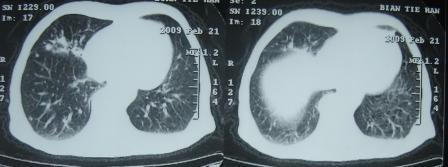

xx 男 63岁 发热 家属描述有时高热 有时低热 抗酸杆菌阴性 于2月21号 胸片及ct

右肺上叶干酪性肺炎并两肺支气管播散。

考虑右肺上叶干酪性肺炎并支气管播散。

楼主  :谢谢大家发言  我和大家考虑的一样干酪性肺炎并播散